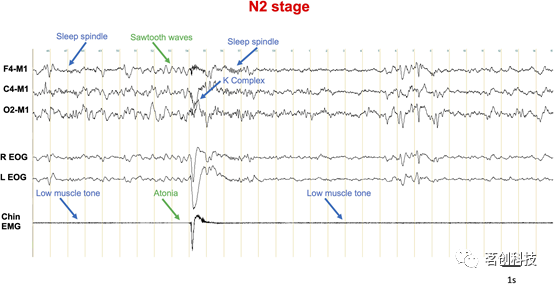

根据AASM的建议,正确识别清醒、非快速眼动(NREM)睡眠、快速眼动睡眠和觉醒需要三种类型的电生理信号。记录这些信号需要至少三个头皮EEG电极,两个位于眼睛两侧的眼电图(EOG)电极和两个放置在颏上方和下方的颏肌电图(EMG)电极,以及位于颏下方的第三个备用电极。头皮EEG电极根据10-20国际系统放置在额叶(F3和/或F4)、中央(C3和/或C4)和枕叶(O1和/或O2)区域,并以双侧乳突电极为参考。也可以使用与参考通道C4-M1相关联的中线双极通道(Fz-Cz和Cz-Oz)。EOG也以参考蒙太奇进行记录,两个EOG电极都参考同侧乳突电极。只有颏EMG通道是双极通道。电生理记录以30s为周期。睡眠专家对每个记录时段进行评分,这些时段被称为“卧床时间(time in bed)”,定义为记录开始(关灯)至记录结束(灯亮)的时间。睡眠分期的一个基本原则是,如果一个时段超过50%(15s)具有警觉状态的电生理特征,则认为该时段属于某种警觉状态。如果一个时段有50%由枕区α活动(8-13Hz)组成,或者观察到与清醒相关的特定运动伪迹,如眨眼、与阅读活动相关的眼动或伴随高肌张力的快速眼动,则被认定为清醒状态。如果一个时段至少有50%为4-7Hz的低电压混合频率活动,取代患者产生α节律的α活动,则该时段为N1期。这种EEG活动可能与N1和N2期出现的缓慢眼动和/或顶部尖波有关。对于未产生α节律的人,N1期的第一个时段是由于:i)至少有50%的EEG频率在4-7Hz之间的θ频段,且背景EEG活动比清醒EEG背景活动减慢至少1Hz;ii)眼球运动缓慢;iii)尖波瞬变。通常在N1期之后,N2期的第一个时段划分为该时段前半期包含K复合波或睡眠纺锤波的时段。如果慢波在一个时段中出现的时间超过20%(6s),则该时段被划分为N3期。慢波定义为频率在0.5-2Hz之间的波,在额区测量的正负峰-峰区间的波幅>75uV,以对侧乳突电极为参考。最后,如果一个时段中有50%以上包含以下所有内容,则将其划分为R阶段(REM睡眠):i)无睡眠纺锤波和K复合波的低电压混合频率EEG活动;ii)颏EMG信号最小,包括在快速眼动期间;iii)该时段的任何时刻都存在快速眼动。同一睡眠阶段的连续性或两个不同阶段之间的转换根据各种规则来定义,此处不做详细说明,这些规则考虑了觉醒或主要身体动作的影响。

基于EEG,EOG和EMG的警觉状态分类

警觉状态之间的波动以大多数身体功能的生理变化为特征,但传统上对清醒、NREM睡眠和REM睡眠的分类和识别仅依赖于三个参数:脑电图(EEG)、眼电图(EOG)和肌电图(EMG)。尽管这种分类方法被广泛使用,但在不同的临床和研究趋势的影响下,这种可能被证明是繁琐和简化的分类正日益受到质疑。在睡眠医学领域,随着对失眠、中枢性嗜睡障碍或睡眠呼吸暂停等睡眠障碍的深入了解,人们正在寻找与临床症状、预后相关性更好、诊断性能更高的生物标志物。在研究方面,越来越复杂的信号分析工具的发展允许从现有数据中提取更多的信息,而对警觉状态时空动力学的理解进展也突出了当前评分方法的局限性。这些标志物大多依赖于EEG高级分析,但也有一些关注其他信号,如心率变异性、血氧饱和度或呼吸信号。